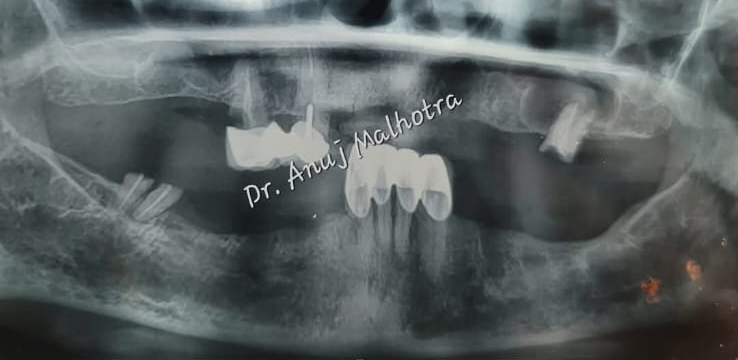

Full Mouth Implant Case

Full Mouth Implants with all Ceramic Crowns